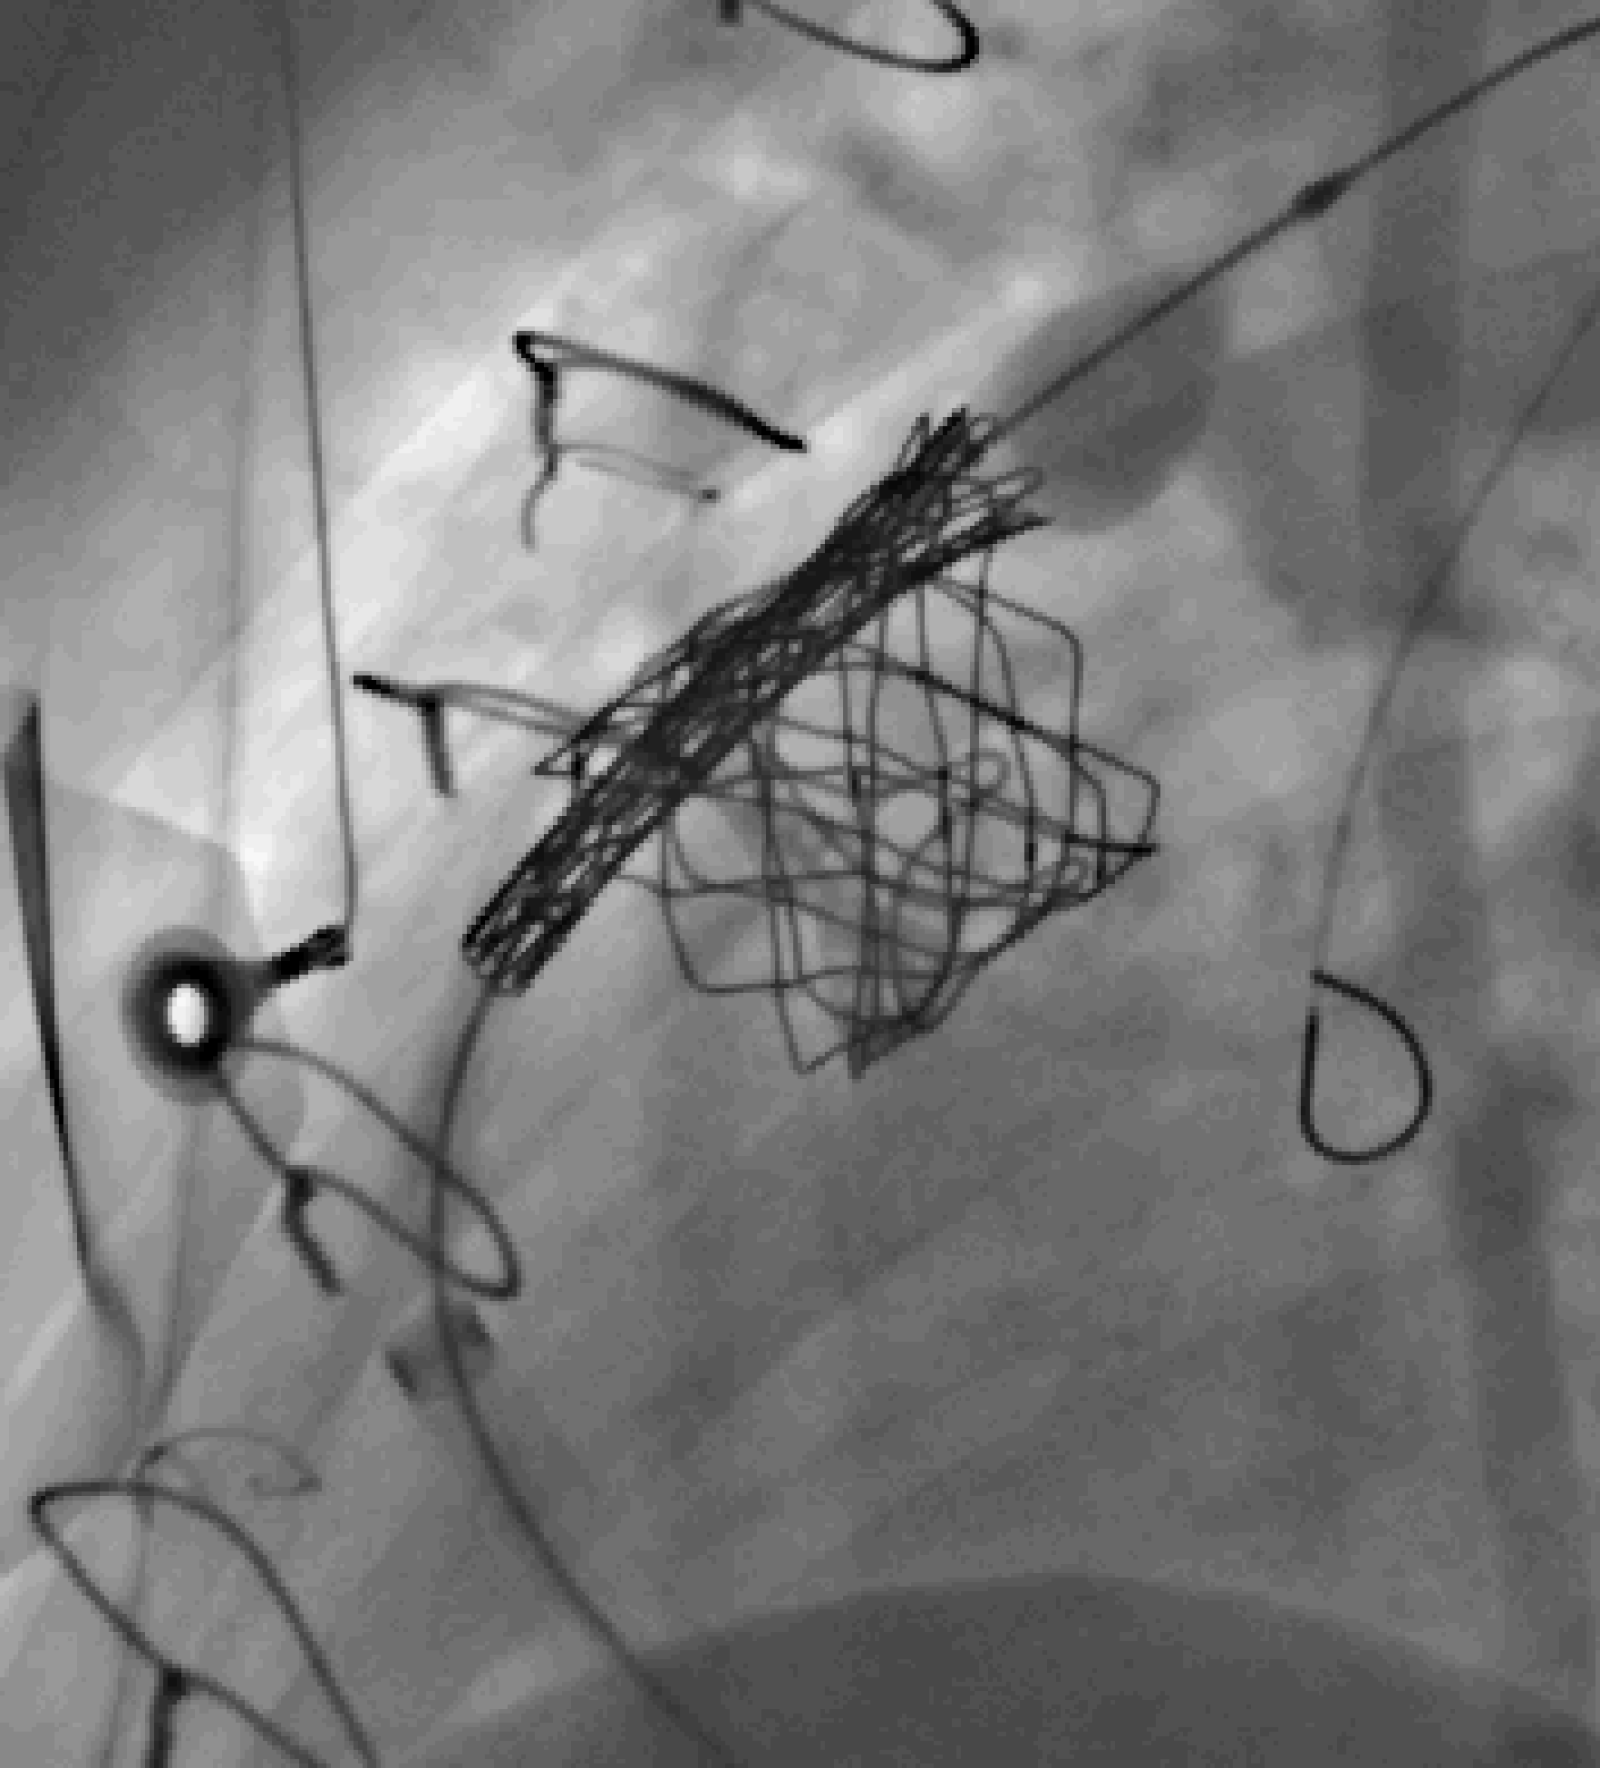

Centrum komplexní péče o vrozené srdeční vady v dospělosti vzniklo  v roce 2015  díky spolupráci  Centra kardiovaskulární a transplantační chirurgie s Interní kardiologickou klinikou Fakultní nemocnice  Brno a nabízí zcela komplexní péči o dospělé nemocné s vrozenou srdeční vadou. Portfolia jednotlivých pracovišť se navzájem doplňují.  Centrum poskytuje ambulantní sledování pacientů se všemi typy vrozených srdečních vad, neinvazivní a invazivní diagnostiku včetně transesofageální echokardiografie s využitím 3D zobrazení.  Centrum kardiovaskulární a transplantační chirurgie Brno provádí operace, reoperace a  intervenční výkony u vrozených srdečních vad a současně se věnuje chirurgické léčbě pokročilého srdečního selhání vč. implantace mechanických srdečních podpor a transplantace srdce ( Tým lékařů , seznam prováděných operačních a intervenčních výkonů).  V rámci Interní kardiologické kliniky FN Brno poskytuje invazivní  řešení arytmií ( radiofrekvenční ablace, kardiostimulace vč. resynchronizační léčby), některé intervence (uzávěry defektů septa síní) , organizaci nekardiálních operací a péči o gravidní včetně porodu probíhají v rámci Interní kardiologické kliniky FN Brno.   Návaznost na kardiologii dětského věku je zajištěna spoluprací s Fakultní dětskou nemocnicí v Brně.  Ambulantní péče probíhá na obou klinikách paralelně.